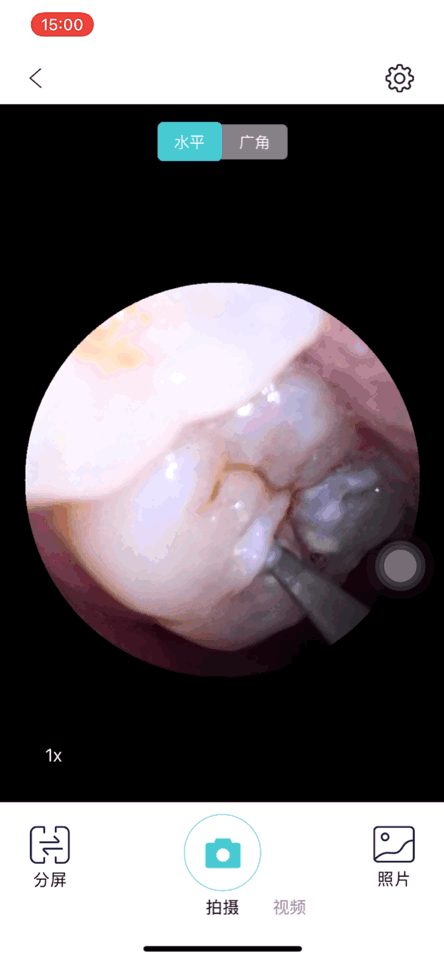

与传统洁牙仪相比,素诺这款洁牙仪最大的特色就是在顶端配备了500W高精度微距内窥镜,这相当于在洁牙仪上安装了一个高清微距摄像头,使用时可以利用WiFi传输的方式在App上实时查看口腔内部图像,彻底摆脱他人的协助,自行使用洁牙仪清洁牙齿。

500W高精度的内窥镜显示效果非常不错,配合顶端的照明灯,可以清晰的看到牙齿上的牙垢和牙菌斑,这对我龋齿的治疗能够起到很强的针对性。使用过程中带给我最大的感受就是画面反应速度非常快,由于使用了无人机专用Wi-Fi芯片,画面延迟速度能够保持在1秒以内,而且没有卡顿感,因而能够更加清晰快速的反应清洁过程。